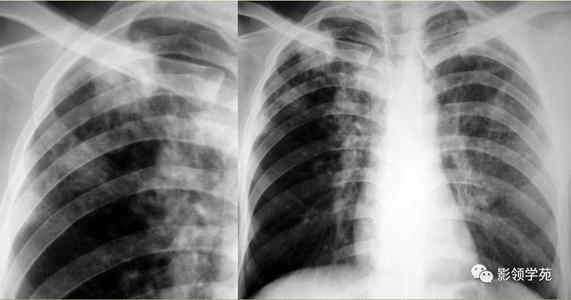

李某,女,56岁。有10余年风湿性心脏病,2年来又出现下肢水肿,偶有颜面水肿,病情反复发作,近因咳喘明显而前来诊治。刻诊:气喘,心悸,下肢水肿,痰稀色白,手足不温,小便不利,头晕目眩,动则喘甚,舌质淡,苔薄白腻,脉虚。辨为心肺水气证,治当温补阳气、利水消肿。给予真武汤与四逆加人参汤合方加味:茯苓9g,白芍9g,生姜9g,白术6g,炙甘草6g,干姜5g,附子5g,生川乌5g(因无生附子,故以生川乌代),红参3g,车前子15g,牛膝24g,薏苡仁15g。6剂,水煎服,每日1剂,每日3服。二诊:气喘、心悸好转,以前方6剂。三诊:手足转温,下肢水肿减轻,又以前方6剂。四诊:动则喘甚明显减轻,又以前方治疗50剂。将前方变汤剂为散剂,每次6g,每日3服,巩固治疗半年。随访2年,一切尚好。